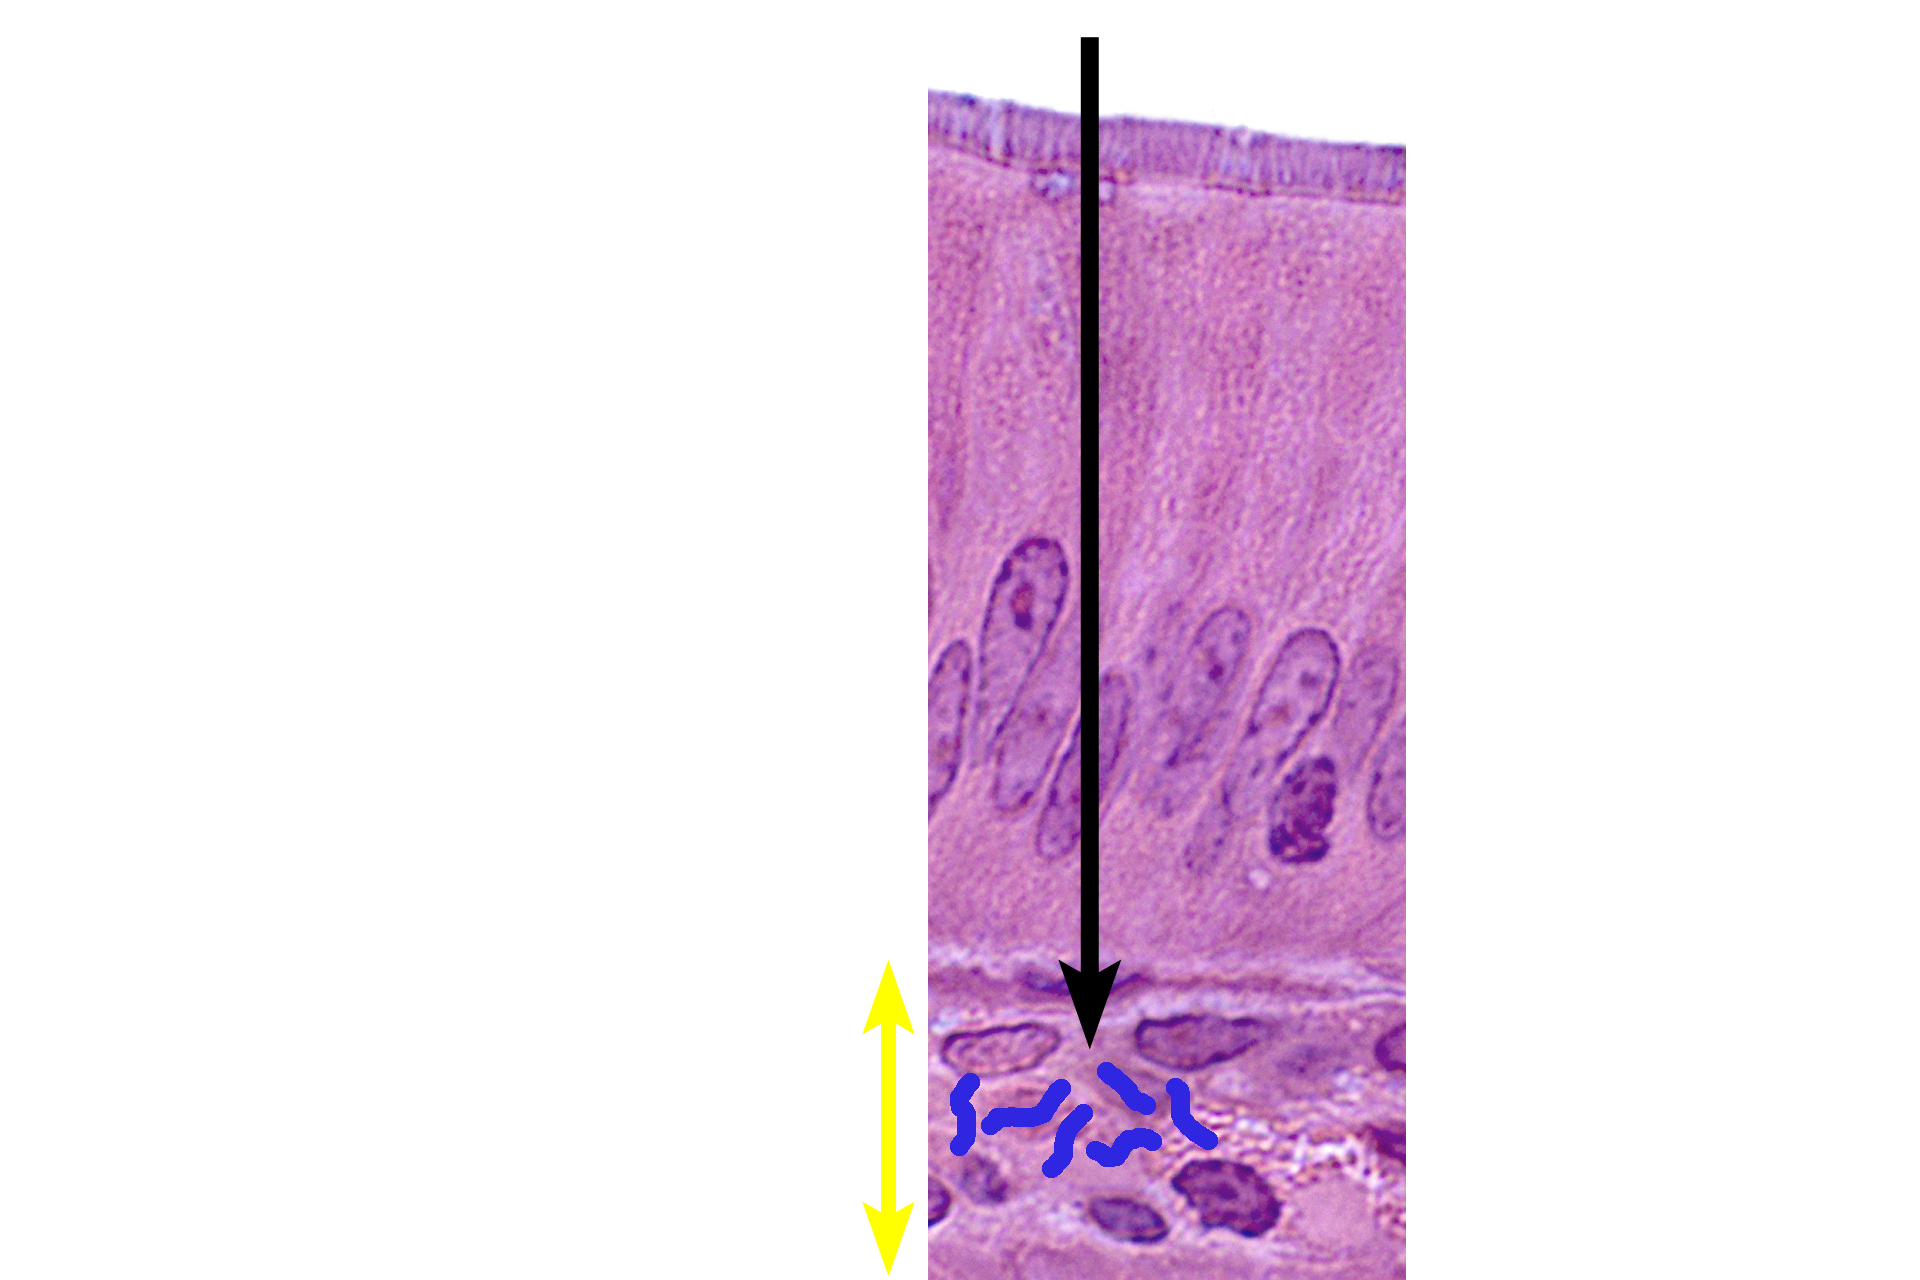

Epithelial membranes, such as the epidermis of skin or mucosae lining internal organs, e.g., the digestive system (shown above), serve as physical barriers against entry of pathogens and toxins. Epithelia are a components of the innate immune system that are present at birth and form the so-called “first line of defense”. 1000x

The epithelium provides a physical barrier to microbe entry along with secretions on its surface, such as digestive enzymes and stomach acid that destroy microorganisms. Epithelia may also contain wandering immune cells, like macrophages, that provide local protection through phagocytosis and recruitment of additional immune cells.

If microbes penetrate the epithelium they enter a connective tissue layer, such as the dermis of skin or lamina propria of a mucosa. There, they are met with a variety of internal defenses consisting of phagocytic and natural killer cells as well as chemical defenses including complement activation and inflammation. All these defenses are components of the innate immune response.